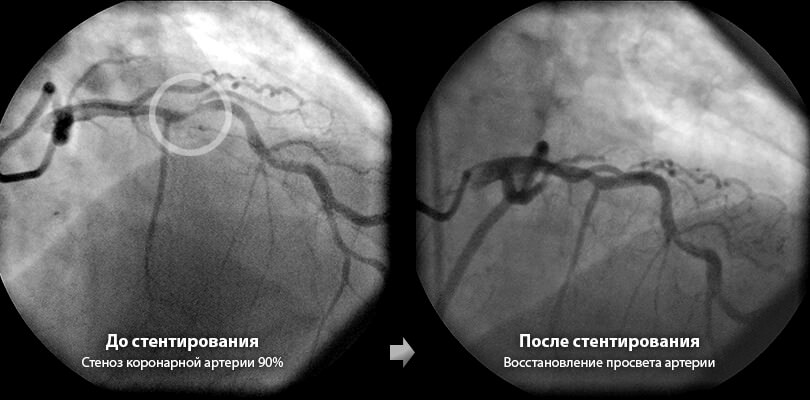

Использование такой технологии позволяет существенно сократить риск рестеноза, а стоимость их существенно выше, чем обычных. Кроме того, при введении такого стента сроком до 12 месяцев нужно принимать антитромбоцитарные препараты, чтобы предотвратить возникновение тромбоза. Такие стенты рекомендуется устанавливать в сосудах небольшого размера, где вероятность закупорки существенно повышается.